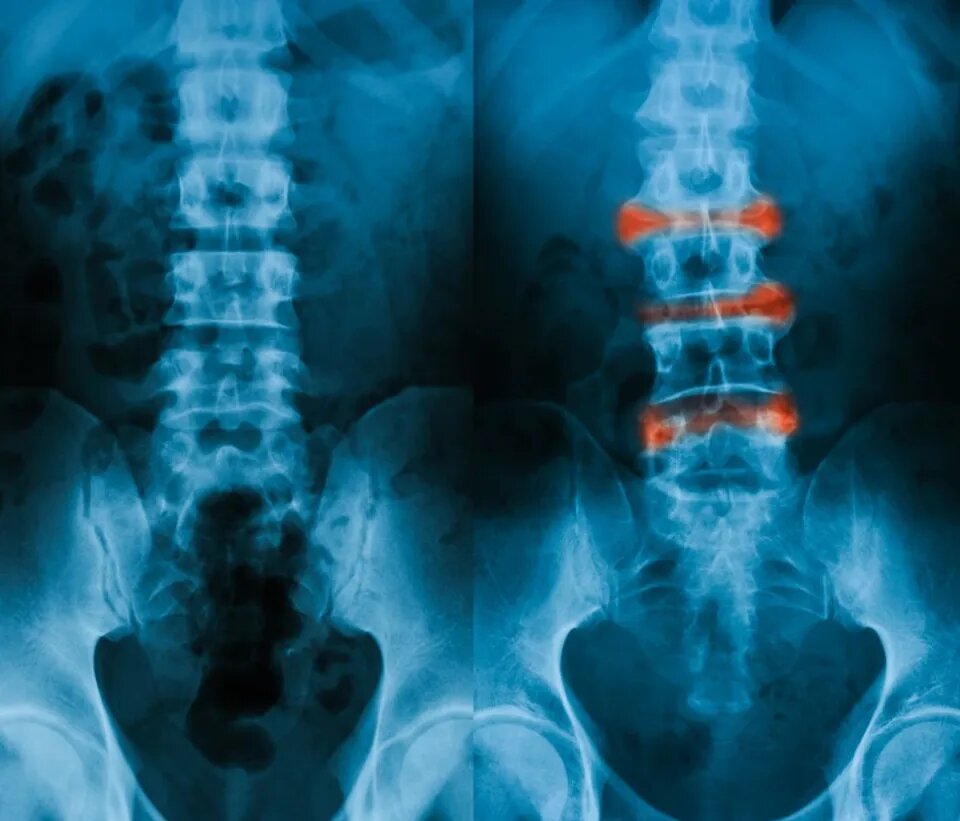

Болезнь Бехтерева. Четыре причины с точки зрения ТКМ и методы лечения.

Диагностика и лечение анкилозирующего спондилита (болезнь Бехтерева) в традиционной китайской медицине основаны на таких принципах, как питание печени и почек, улучшение кровообращения и устранение застоя крови, устранение холода и сырости, устранение жары и детоксикация. В дополнение к пероральному приему лекарств также применяются наружные методы лечения, такие как аппликации, иглоукалывание и прижигание. Лечение требует всестороннего учета физического состояния пациента и разработки индивидуальных планов лечения. В западной медицине диагноз един на основе проведенных исследований и анализов, однако точно сказать почему у человека появилось это заболевание и прогрессирует точных ответов нет. В китайской медицине немного другой подход. Это касается не только анкилозирующего спондилита, а в целом всех заболеваний. Китайский врач ищет корень, а то, что беспокоит пациента – то, что «наболело» это симптом. Итак, давайте разберем, что в ТКМ может стать первопричиной болезни Бехтерева. 1. Н

В западной медицине диагноз един на основе проведенных исследований и анализов, однако точно сказать почему у человека появилось это заболевание и прогрессирует точных ответов нет. В китайской медицине немного другой подход. Это касается не только анкилозирующего спондилита, а в целом всех заболеваний. Китайский врач ищет корень, а то, что беспокоит пациента – то, что «наболело» это симптом. Итак, давайте разберем, что в ТКМ может стать первопричиной болезни Бехтерева.